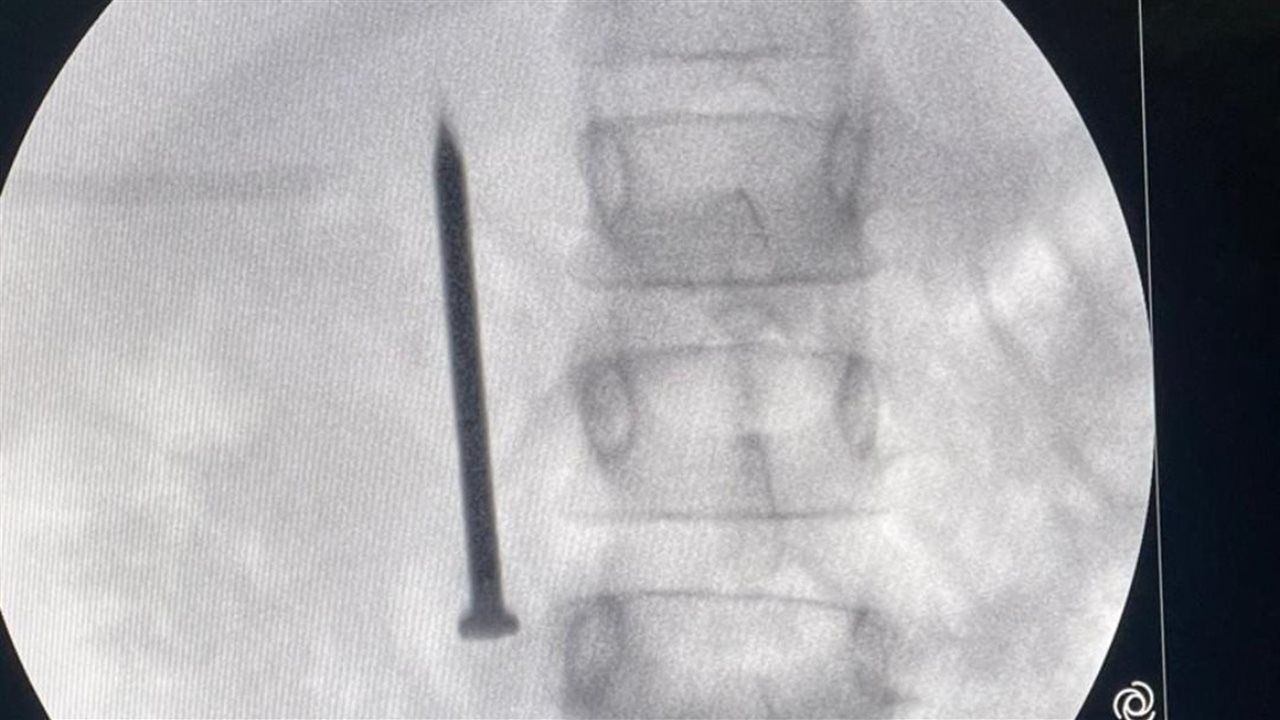

أعلن الدكتور أحمد القاصد، رئيس جامعة المنوفية، عن نجاح فريق طبي متخصص بوحدة مناظير الجهاز الهضمي بمعهد الكبد القومي في إنقاذ حياة طفلة تبلغ من العمر 7 سنوات، بعد ابتلاعها مسمارًا معدنيًا حادًا يبلغ طوله 4 سنتيمترات.

وأوضح رئيس الجامعة أن الفريق الطبي تمكن من استخراج المسمار الذي وصل إلى الجزء الأول من الأمعاء الدقيقة عبر إجراء منظار طارئ لم يستغرق سوى 20 دقيقة، متجنبًا بذلك خطر الثقب أو النزيف أو الانسداد المعوي الوشيك، حيث غادرت الطفلة المستشفى بصحة جيدة بعد التدخل الطبي السريع.

من جانبه، أكد الدكتور أحمد صيرة، أستاذ طب كبد الأطفال ورئيس وحدة مناظير الأطفال وقائد الفريق الطبي، أن استخدام المنظار كان الخيار الأمثل لتجنب إجراء عملية جراحية مفتوحة أكثر إرهاقًا للطفلة، مشددًا على أهمية التدخل السريع في مثل هذه الحالات لتفادي مضاعفات محتملة مثل الثقب أو النزيف أو الانسداد المعوي.